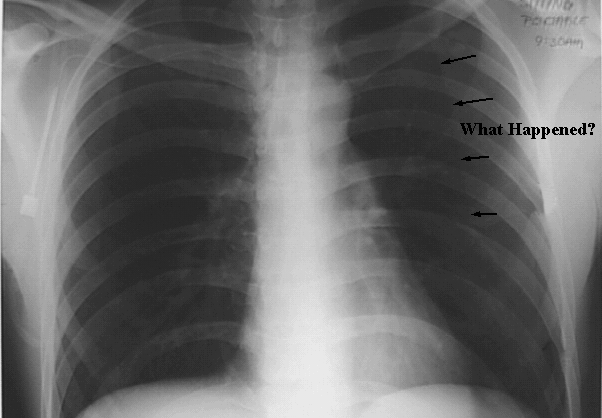

Thorax- Chest Pneumothorax

Arrows: Lung markings disappeared.